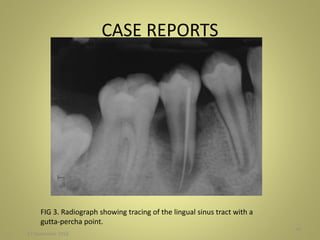

radiolucency (Fig. 2), and a lingual sinus tract was present that

traced to the apex of the tooth (Fig. 3).

FIG 3. Radiograph showing tracing of the lingual sinus tract with a

gutta-percha point.

CASE REPORTS 27 November2016 50 FIG 3. Radiograph showing tracing of the lingual sinus tract with a gutta-percha point.